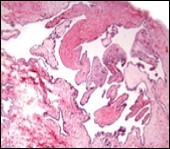

Alternatively, cutaneous ciliated cyst can be lined by non ciliated cuboidal or columnar epithelium with intermingled intercalated, dark or round peg cells. Foci of squamous metaplasia can be occasionally exemplified in the adherent epithelium whereas mucinous cells or apocrine-like features are exceptional 6, 8. Figure 1, Figure 2, Figure 3, Figure 4, Figure 5, Figure 6, Figure 7, Figure 8, Figure 9, Figure 10, Figure 11, Figure 12. 11, 12, 13, 14, 15, 16, 17, 18, 19.

Figure 1.Ciliated cutaneous cyst lined by pseudostratified ciliated columnar epithelium and a supporting fibro-connective tissue stroma 11.